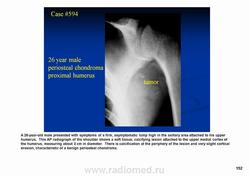

Периостальная хондрома (син.: юкстакортикальная хондрома, паростальная хондрома редкая доброкачественная опухоль, состоящая из зрелой хрящевой ткани и расположенная над надкостницей. Обычно она разрушает наружную часть коркового слоя, но не прорастает в костно-мозговой канал. Мужчины болеют в два раза чаще женщин. Типичная локализация - проксимальный конец плечевой и бедренной кости дистальный конец бедренной кости, а также фаланги. В редких случаях одновременно поражается несколько костей. Периостальная хондрома обнаруживается большей частью в метафизарной части, лишь у 30 % больных поражаются диафизы. Опухоль достигает в среднем 2-3 см в диаметре. Она окружена зоной остеосклероза и сопровождается периостальным остеогенезом, так что на границе опухоли с костью образуется грушевидное углубление с четкими контурами. Под микроскопом периостальная хондрома имеет тонкие контуры, она как бы погружена в корковый слой и покрыта надкостницей, как тонкой скорлупой. На разрезе ее ткань синюшно-серая или белая, хрящевые элементы обладают дольчатым строением. Участки обызвествления имеют вид желтовато-белых вкраплений. Эта опухоль состоит из гиалинового хряща, дольки которого разделены фиброзными прослойками или костными балками, местами обызвествленными. Кое-где отмечается проникновение опухолевых клеток в костномозговой канал, на большем же протяжении внутренний контур образован компактной костью.

Дифференциальная диагностика представляет известные трудности в тех случаях, когда периостальная хондрома имеет сходство с юкстакортикальной хондросаркомой.